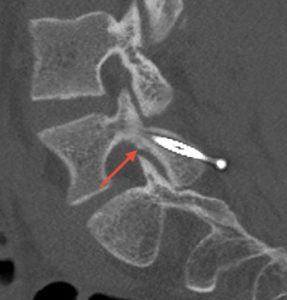

FM: Pars fracture repair is a very exciting area in spine surgery, particularly for younger patients and athletes, because it offers the ability to treat the source of pain while preserving motion. My focus has been on applying robotic technology to direct pars repair in carefully selected patients. As the highest-volume surgeon in New Jersey performing outpatient robotic pars repairs, I am currently studying my outcomes. We’re seeing that robotics can transform what was traditionally a more invasive procedure—often requiring 1-2 night hospital stays—into an outpatient surgery using small percutaneous incisions.

Patients are returning to sports as early as six to eight weeks post-operatively. While long-term comparative data is still evolving, robotics may improve reproducibility, shorten recovery, and maintain similar healing rates and long-term outcomes compared to traditional open techniques.

Images show pre-op CT and post-op CT, showing the healing, as well as a picture of the incisions. Image credits: Dr. Farah Musharbash

FM: Thankfully I have had many highlights, and every patient story is meaningful. One was performing an emergency surgery on a young patient who was paralysed from a spontaneous epidural hematoma and seeing him walk into my office unassisted two weeks later. Another was a 15-year-old athlete going home the same day after robotic pars repair—and later returning to soccer within three months. Those moments are incredibly meaningful.